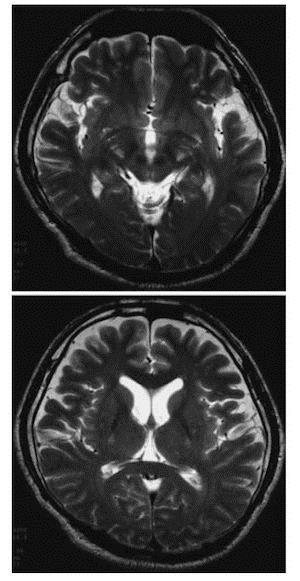

ALS診断のための検査:MRI

ALSでは通常MRIでは異常所見は見られないが、他疾患の鑑別が主な役割。

時にFLARIRやT2強調画像で、皮質脊髄路にそって高信号が認められることがある。

内包後脚および大脳脚に淡いT2高信号が認められる。

大脳脚レベル以下や中心前回皮質下まで続く高信号はALSの病的変化と考えられる。

T2強調像や磁化率強調像で中心前回皮質の信号がみられる頻度が高い。